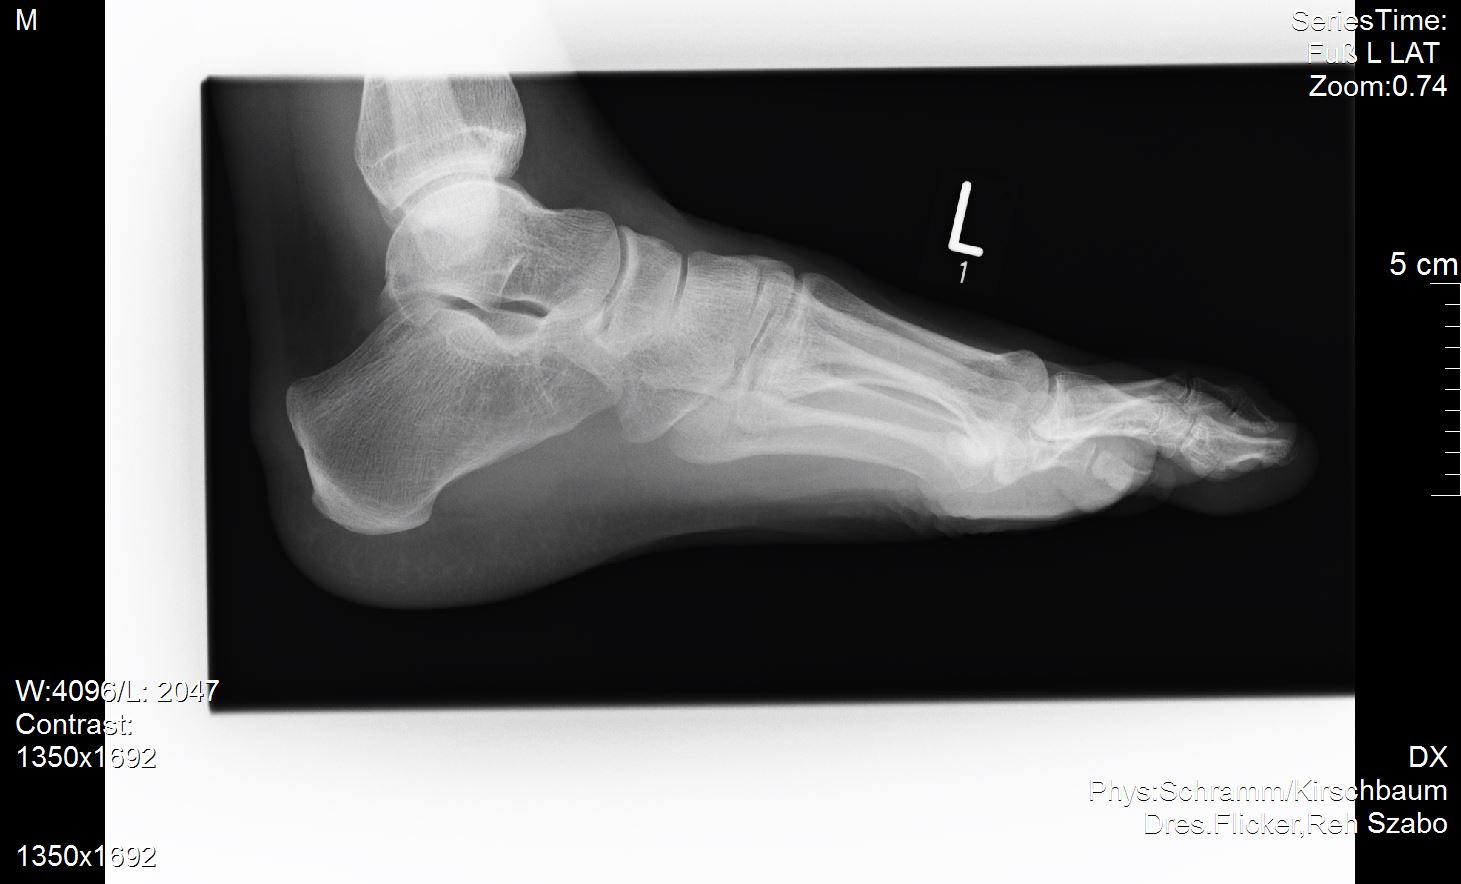

Ich versuche mal meine Röntgenbilder anzuhängen. Vielleicht ist ja ein Experte unter uns der dazu was sagen kann?

Ich habe außer dem mir diagnostizierten Spreizfuß nach oben stehende Zehen. Weiß nicht genau ob man dies Hammerzeh oder Krallenzeh nennt was ich habe aber es geht in die Richtung.